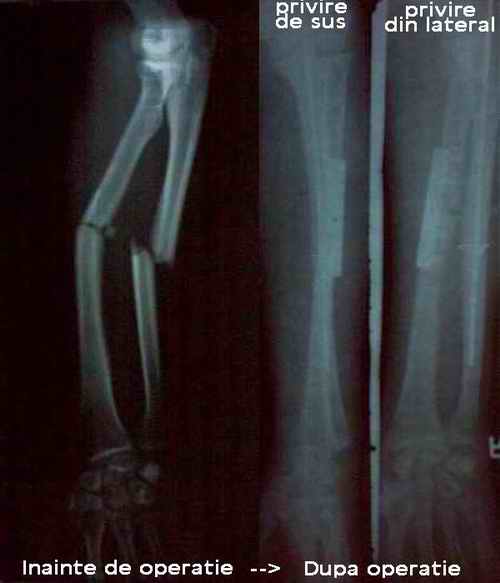

Bratul lui Flavius

accident cu bicicleta soldat cu fractura la ambele oase ale mainii, rezultat tija si restul ....

Clavicula rupta cu deplasare